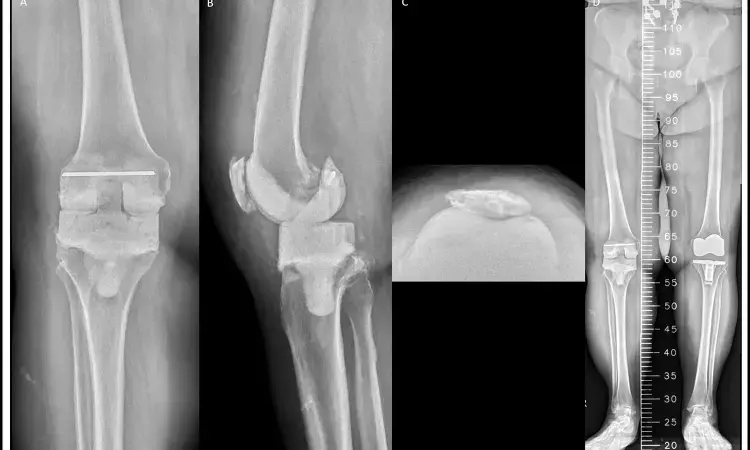

A large register-based study published in BMJ Open has reported that patients with type 2 diabetes undergoing hip or knee replacement surgery face a higher risk of long-term mortality but not an increased risk of reoperation. The research analyzed outcomes from more than 190,000 procedures recorded in Swedish national registers, making it one of the most comprehensive evaluations of diabetes and joint replacement to date.

According to the study, type 2 diabetes was linked to a greater likelihood of death after both hip and knee replacement, while the risk of requiring additional surgery remained unchanged compared to patients without diabetes. Short-term adverse events, such as complications occurring soon after surgery, were only minimally affected.